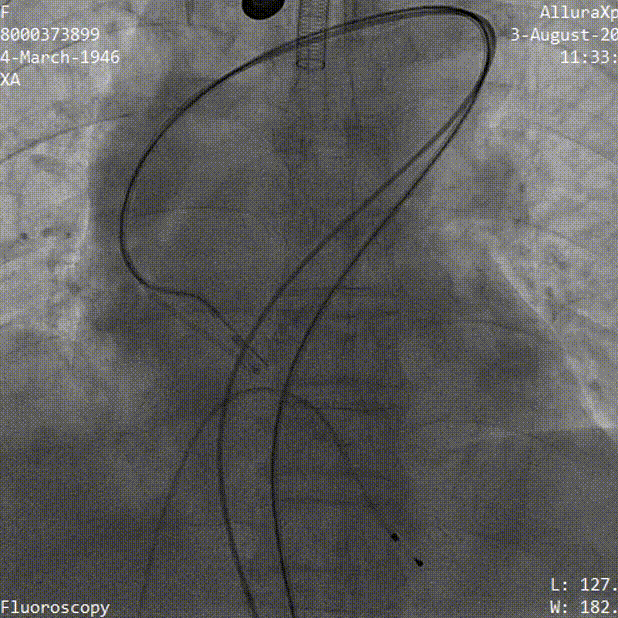

TaurusElite AV23瓣膜初始定位

瓣膜逐步释放至工作位过程

工作位造影 瓣膜位置良好